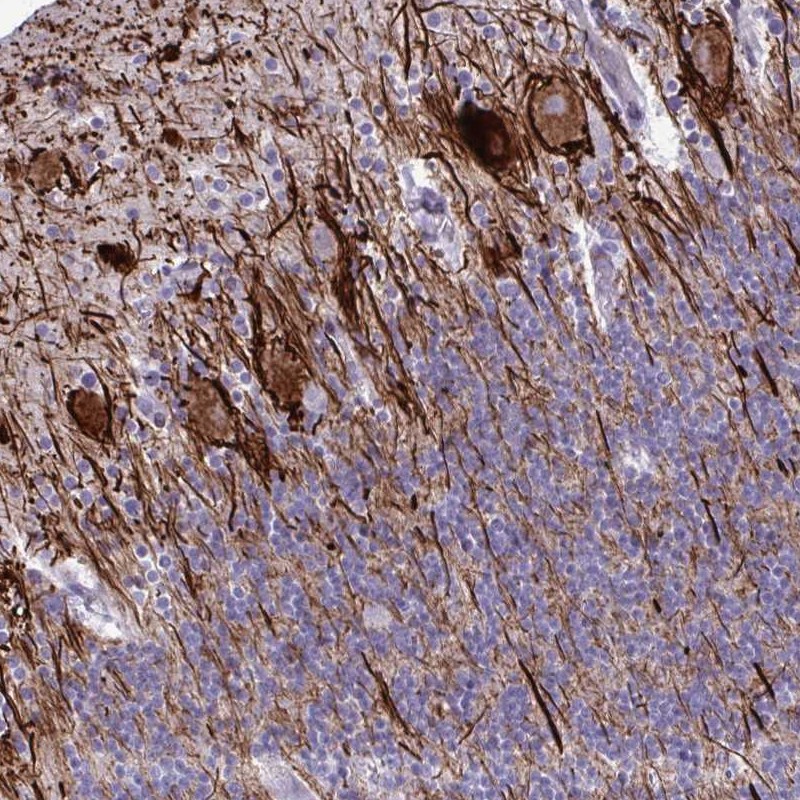

Immunohistochemical staining of human cerebellum shows distinct positivity in processes.